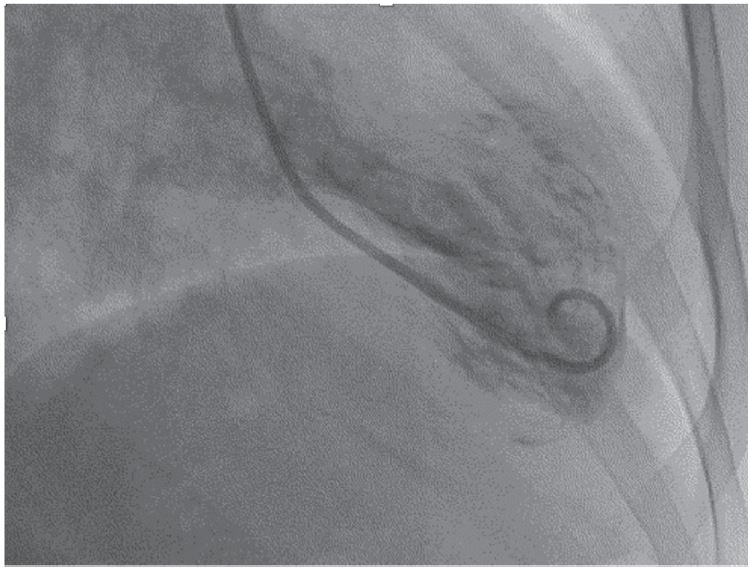

Tromboembolismo pulmonar y síndrome de Takotsubo como causantes de paro cardiorrespiratorio

IMÁGENES EN CARDIOLOGÍA